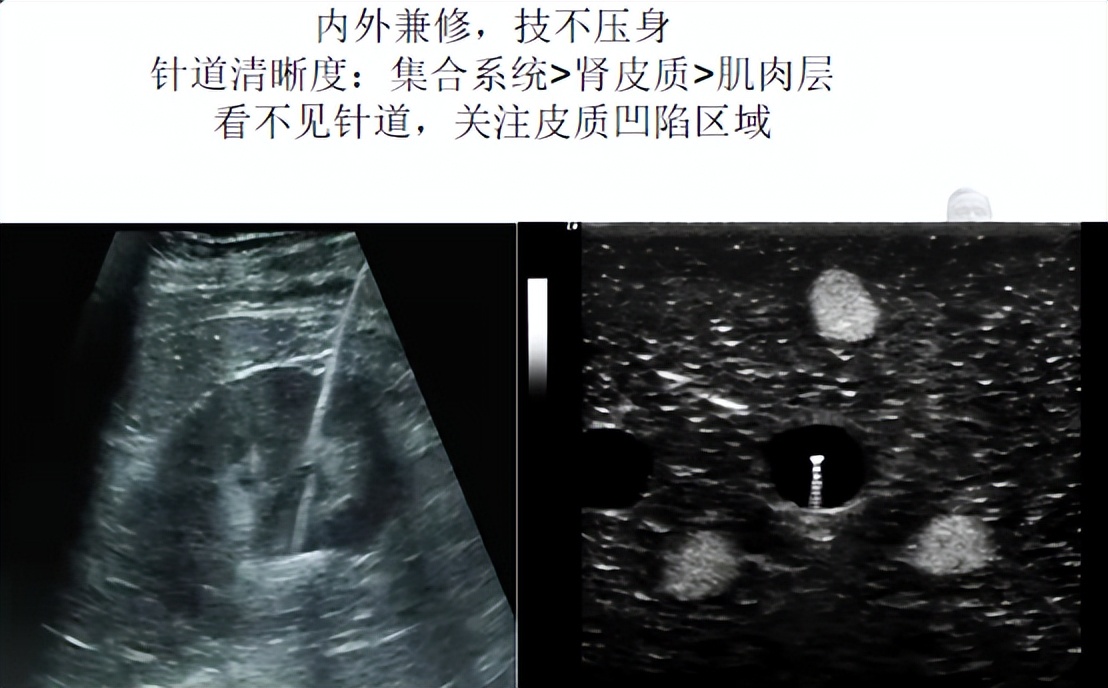

B超引导穿刺有平面内和平面外两种手段。B超探头与皮肤一面之缘,要求:1.垂直,不偏不倚;2.紧贴,相依相靠。

平面内:相向而行、有迹可寻。平面内穿刺是关键领域亮剑,将目标肾盏置于和超声左侧扇面边缘成30°处,盏颈同轴一见倾心,只见云来遮、雾来盖,云里雾里放光彩。

平面外:若隐若现、抛头露面。平面外穿刺为敏感部位*点露**,以目标肾盏垂直对应的探头侧方皮肤作为穿刺点,紧贴探头进针。关注目标动静,扶墙(通道)花影动,疑是玉人(针芯)来。李商隐体会心有灵犀一点通,说的是使出灵犀一指开路,抵达目标肾盏点到为止。

望穿秋水,水到渠成。穿刺到位的标志是拔芯见水。水不出来,或许是穿刺针与集合系统还有隔膜,不捅破这层膜,导丝就尚未和肾脏发生关系。肾积脓也可能抽不出水,可以通过注水回抽鉴别。一句话,没湿别冒进。

B超引导下穿刺开路就那么回事:(探头)下盘要稳,进针要准,置鞘要顺。跟着导丝走,肾脏在招手。见好就穿,见缝就钻,屡试不爽。